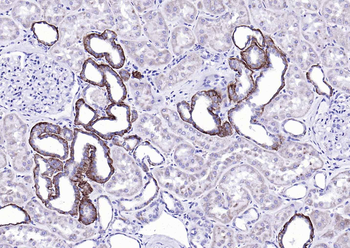

IHC-P staining of rat liver tissue using Emp1 antibody (2.5 ug/ml)

Immunohistochemical staining of rat liver tissue using Emp1 antibody (2.5 ug/ml)